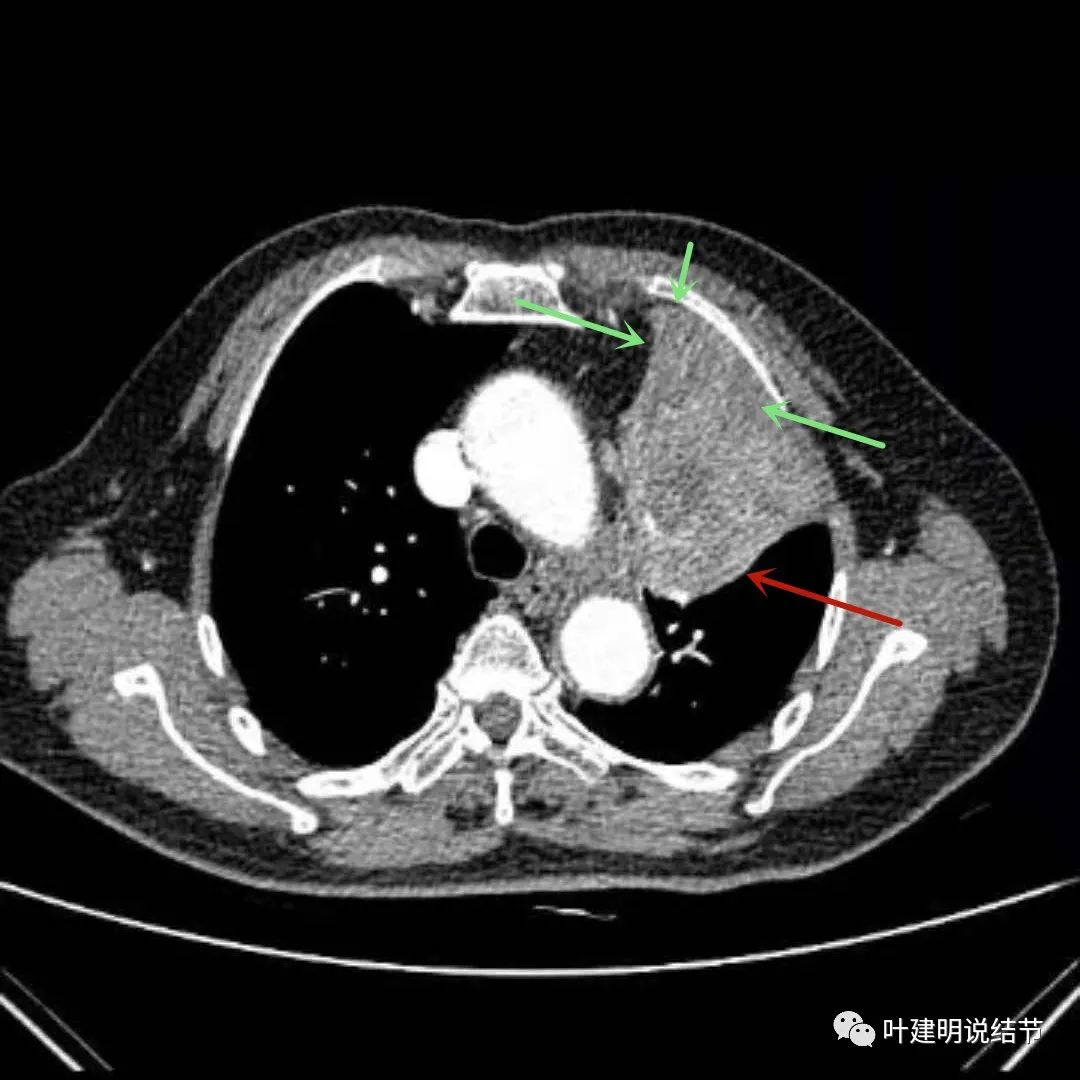

上图绿色箭头所指区域考虑为肺不张,红色示肿瘤处,桔色箭头所指处是被肿瘤包绕的肺动脉分支

上图绿色箭头所指区域考虑为肺不张,红色示肿瘤处且有不均质与膨胀性,桔色细箭头所指处是被肿瘤包绕的肺动脉分支起始部,粗桔色箭头示肺动脉与肿瘤间紧密愈着,考虑有侵犯肺动脉